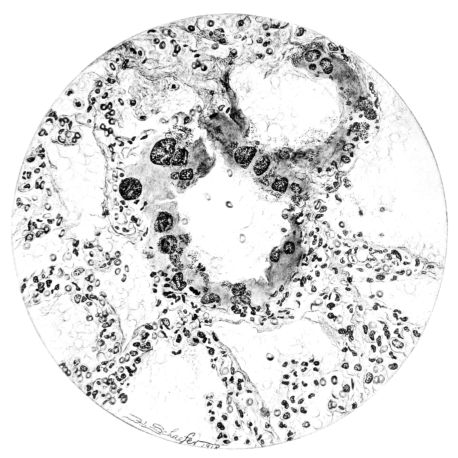

FIG. III. AUTOPSY NO. 90. DRAWING FROM A LESION OF THE TRACHEA (SOMEWHAT OLDER THAN THAT ILLUSTRATED IN FIGURE II). THE MUCOSA IS ENTIRELY LACKING. CONGESTION AND EDEMA ARE THE STRIKING FEATURES IN THE SUBMUCOSA. THE NECROTIZING PROCESS HAS EXTENDED INTO THE MUCUS GLANDS. THIS IS SHOWN IN THE LOWER PICTURE.

The changes are less marked, perhaps, in the trachea than in its finer ramifications. The mucosa is constantly more or less destroyed and large areas, usually focal, are entirely devoid of their epithelial covering. This is replaced by a sparse exudate, composed largely of red blood cells, mucus, a small amount of fibrin, and nuclear fragments (Fig. II). It may dip into the submucosa for a short distance, but usually these indentures are associated with the ducts of the mucous glands into which the inflammatory reaction extends. A more striking feature than the exudate, however, is the edema and the congestion of the submucosa. The loose areolar tissue of the submucosa is spread widely apart, and throughout it distended blood vessels are very conspicuous. Occasionally such a vessel is broken and actual hemorrhage appears in the submucosa. Occasionally, too, the inflammation extends down the duct to the mucous gland itself, and here, also, aplastic inflammatory reaction is evident, inasmuch as the acini now stain intensely red with the cells undifferentiated from each other and specked here and there by broken remains of the dead nuclei (Fig. III). After the disease has continued for a short period, even at the end of five or six days, some regeneration of the epithelial lining may be seen (3) (Fig. IV). But despite this, the acute picture persists, and there goes on, side by side, an attempted repair characterized by epithelial regeneration and the same evidence of acute change. Since the lesion is essentially a superficial one, scars or contractures of any extent are not encountered in the trachea, even in examples of the disease that have ended fatally only after many weeks.[4]